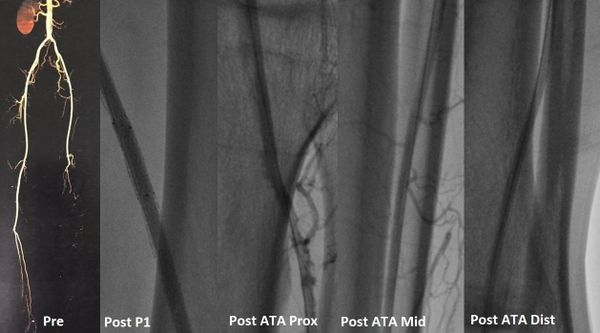

جراح أوعية دموية متخصص في علاج الوحمات الدموية للأطفال - انسداد الشرايين - قدم السكري والغرغرينا -علاج دوالي الساقين بالليزر

استشاري جراحة الأوعية الدموية و القسطرة التداخلية الطرفية